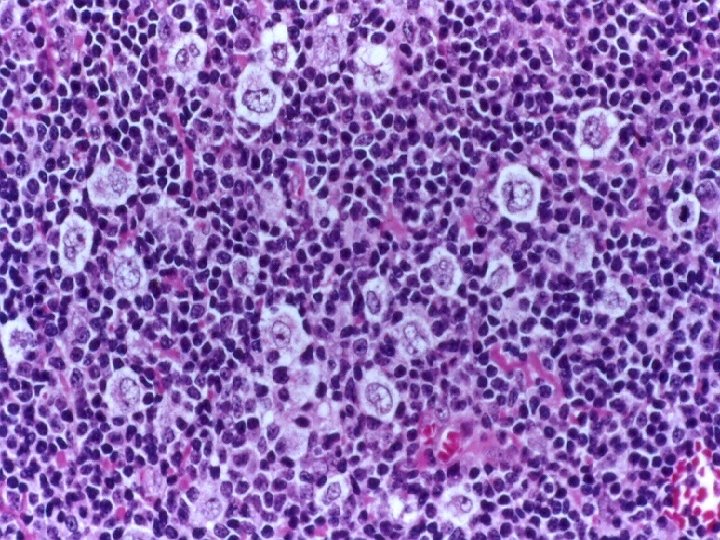

Linfoma de Hodgkin Clásico Rico en Linfocitos Ø Tumor difuso con células de Reed-Sternberg

Linfoma de Hodgkin Clásico Rico en Linfocitos Ø Tumor difuso con células de Reed-Sternberg de tipo clásicas frecuentes, con un trasfondo de linfocitos, escasas células plasmáticas y escasos eosinófilos. Ø Célula de Reed- Sternberg tiene una morfología e inmunofenotipo clásico Ø Patrón nodular con ausencia de CD 21+